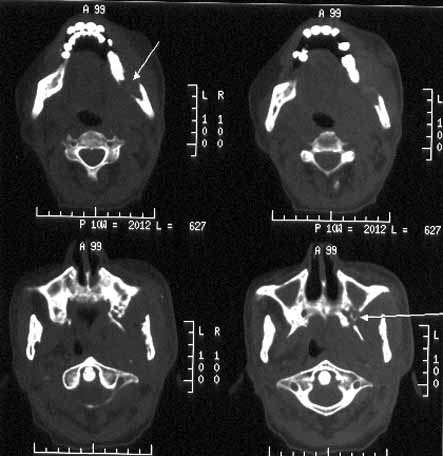

男性,60岁,鼻咽癌放疗后12年,5年前复发再行放疗后缓解。近期牙痛,牙龈活检见鳞癌细胞。

ct诊断:鼻咽癌复发,侵及左下颌骨、上颌骨及颞下窝。